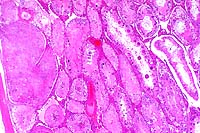

2x

obj

20x

- Case 18-2. Spinal cord. Neuronal degeneration, necrosis,

and loss is responsible for fragmentation & collapse of spinal

cord gray matter. At 20x, neuronal cytoplasm has increased eosinophilia

and nuclei are karyorrhectic.

- AFIP Diagnosis: Spinal cord, ventral gray horns: Neuronal

necrosis, bilaterally symmetrical, breed unspecified, porcine.

- Hematoxylin and eosin stained transverse and longitudinal

sections of spinal cord of the lumbosacral area are submitted.

There is bilaterally symmetrical degeneration and necrosis of

the motor neurons in the ventral horns of the grey matter. These

changes comprise swelling, chromatolysis, increased eosinophilia,

fading of nuclear membranes, and nuclear pyknosis. In the surrounding

grey matter, there is marked oedema characterized by vacuolation

of the neuropil, dilation of perivascular and perineuronal spaces,

presence of eosinophilic fibrillar to floccular material (probably

protein) in the perivascular spaces, and mild swelling of astrocytes.

Small arterioles in the grey matter reveal mild swelling of endothelial

cells as well as mild fibrinoid change of the walls. A few small

foci of perivascular and interstitial haemorrhage can also be

seen within the grey matter. In the white matter, there is marked

diffuse vacuolar change with mild to moderate axonal swelling.